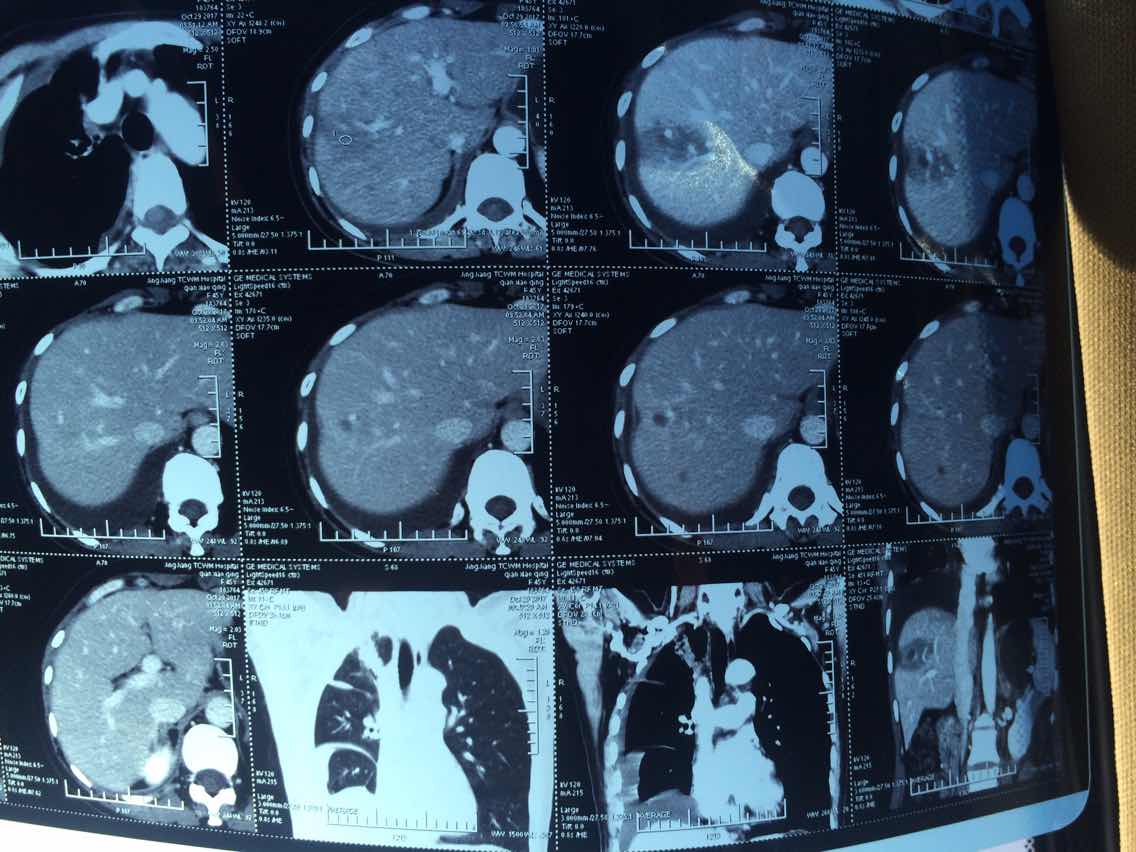

2017.10.29ct

2017.10.29